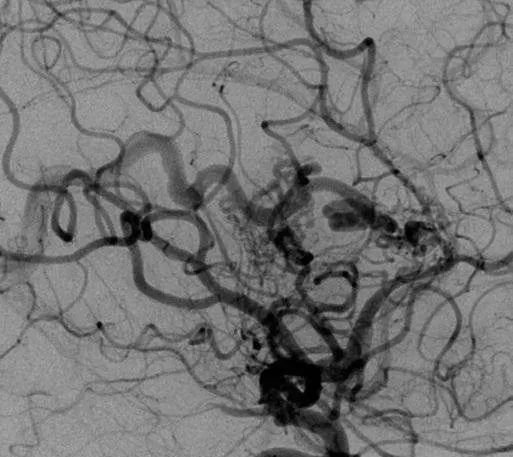

該AVM由ACA/PcaA分支、ACoA穿支和mPChA供血[右側(cè)ICA造影